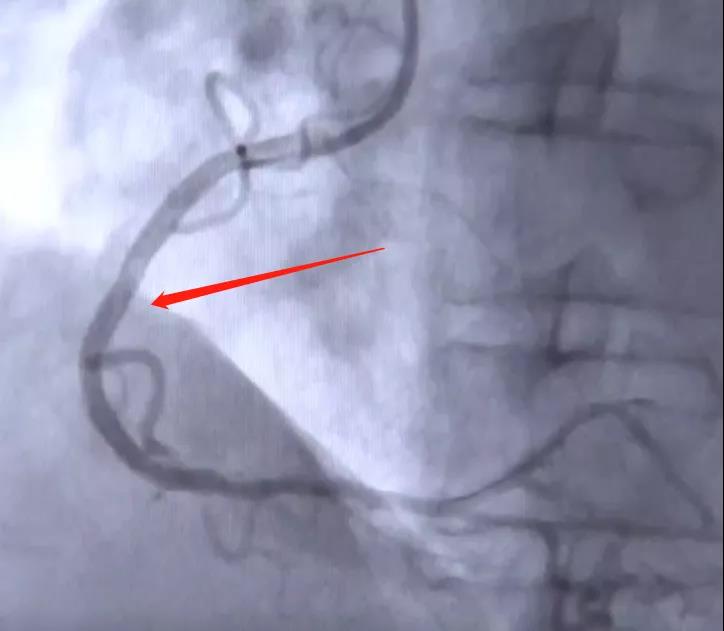

回旋支‍‍大概有50%左右的狭窄,中段这个位置,几乎就剩一条线了,这个地方‍‍有可能有95%甚至99的狭窄。一旦他的血的需要量很大的时候——也就是干体力重活的时候——这支血管肯定不可能‍‍做到很很充分的供血。‍